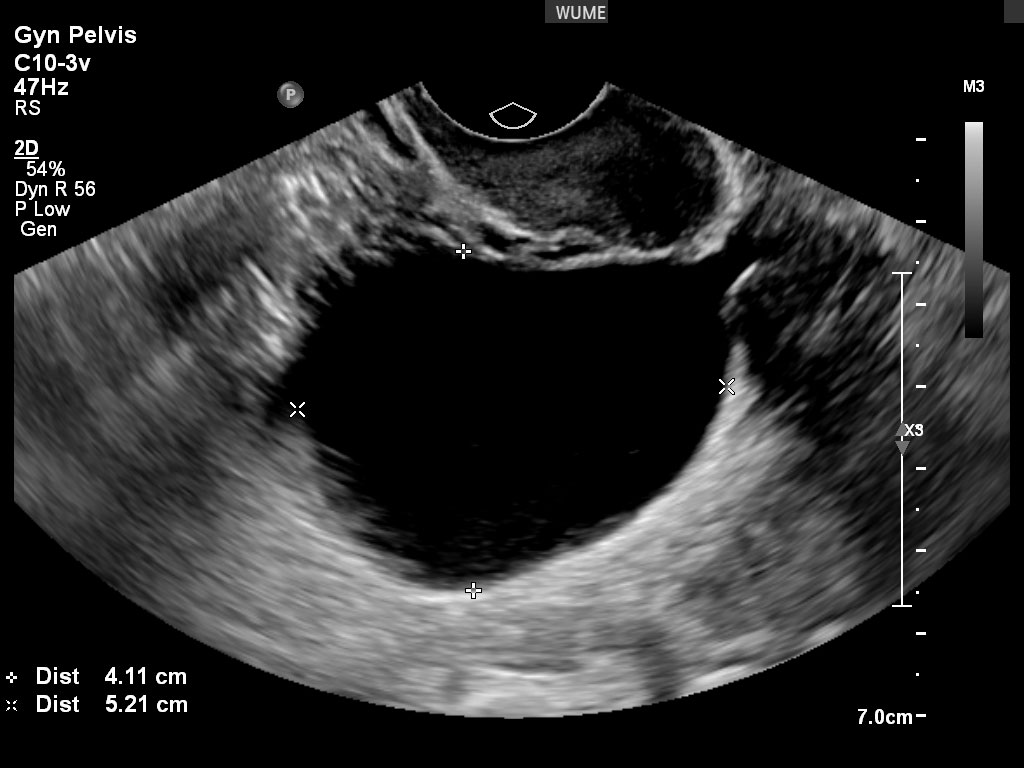

کیست های تخمدان

تخمدان ها اندام های فعالی هستند که به طور طبیعی در طول چرخه قاعدگی "کیست" کوچک ایجاد می کنند. اینها کیست هایی با عملکرد طبیعی تخمدان هستند. این کیست های طبیعی معمولاً به راحتی قابل تشخیص هستند. کیستهای مهمتر را میتوان در طول اسکن تشخیص و ارزیابی کرد و هر یافته مهمی را که در گزارش برای پزشک شرح داده شد و همچنین در زمان سونوگرافی با شما در میان گذاشت.

تشخیص و پیگیری کیست